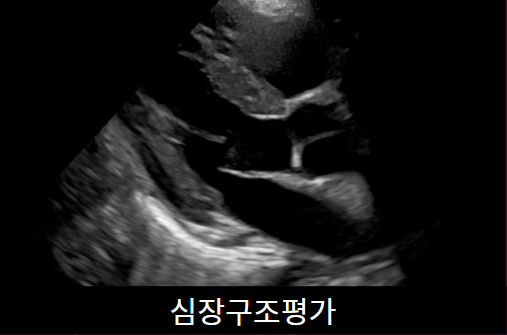

심장초음파

심장초음파는 흉통, 호흡곤란이 있을 때 심장의 구조적 이상을 평가하기 위해 시행합니다. 심근경색, 판막질환, 심부전을 진단하는데 많은 정보를 제공하는 검사입니다. 약 20~30분 걸립니다.